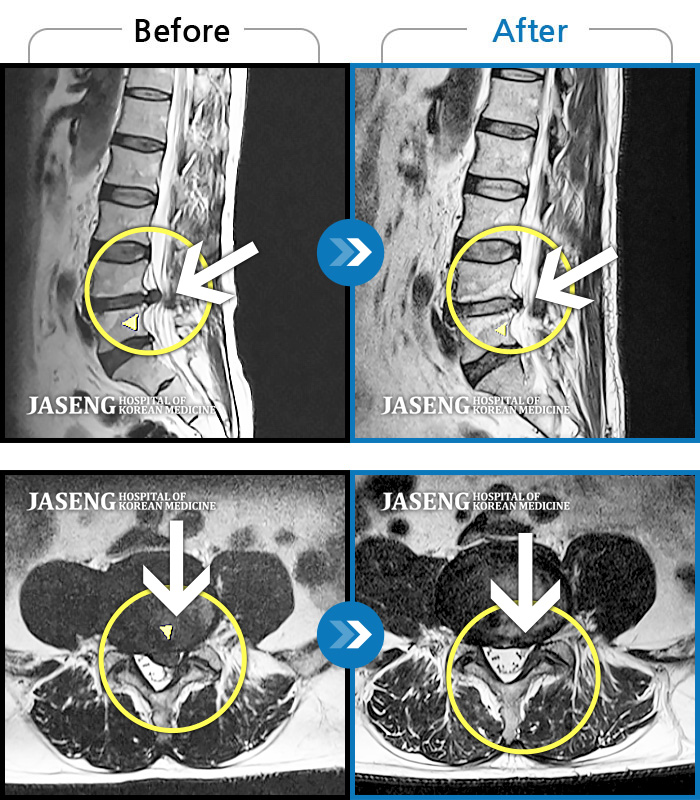

Before

After

환자에게 사전 동의를 받아 동일 조건에서 촬영되었습니다.

개인에 따라 치료 후 부작용이 발생할 수 있으니 의료진과 상담 후 치료를 진행하시기 바랍니다.

양쪽 허리와 골반 통증, 걸을 때 좌측 다리가 당기고 아픔

양쪽 허리와 골반 통증, 걸을 때 우측 다리 당김 및 통증